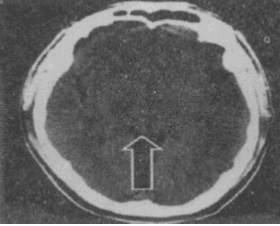

箭头所指的解剖结构是

A.脑桥B.四叠体C.上髓帆D.小脑上蚓E.松果体

B

四叠体是人脑的一个解剖结构,位于脑干的中脑,中脑的背部称为顶盖,由上下两对小丘组成,分别称为上丘和下丘,合称四叠体。